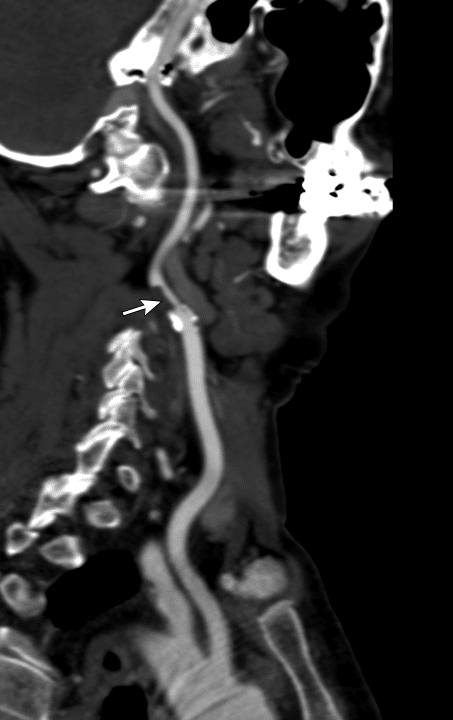

A angiotomografia computadorizada (angioTC) fornece avaliação anatômica detalhada, com boa resolução espacial. É útil tanto na estratificação do grau de estenose quanto na identificação de alterações da parede arterial típicas de arterites ou dissecções. Além disso, a angioTC permite visualizar a presença de trombos ou hematomas intramurais.

A imagem angiotomografia computadorizada (ATC) abaixo demonstra-se uma estenose focal de alto grau em segmento longo da artéria carótida interna esquerda, logo após a bifurcação (seta):